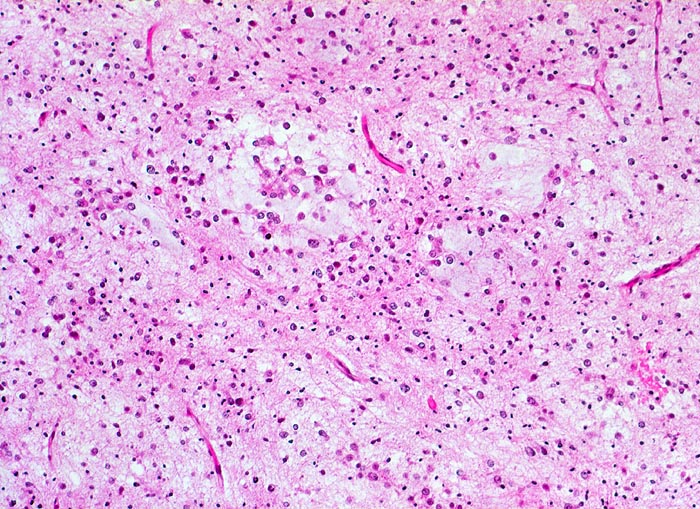

PathoPic ID 5257 - Oligodendrogliom (WHO Grad II)

Oligodendrogliom (WHO Grad II)

maligner Tumor

Hirn frontal

Nervensystem

Das Tumorgewebe enthält zahlreiche kapilläre Gefässe. Das Stroma ist fokal

mukoid degeneriert. Der helle Zytoplasmasaum fehlt in diesem Tumorabschnitt.

Kopfschmerzen und epileptische Anfälle seit zwei Jahren.

Histologie

100